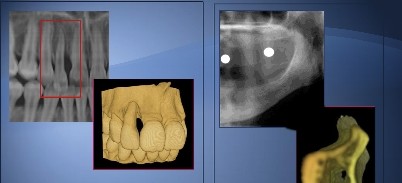

Das CTV-System geht durch seinen quasi analogen Bildverarbeitungsprozess einen neuen Weg und eröffnet Möglichkeiten, genau diesen Anforderungen zu genügen: Der Anwender erhält Darstellungen in gewohnter analoger Qualität – OPG, Fernröntgen und aussagefähige Schnittbilder beliebiger Orte und Winkel. Gleichzeitig werden die benötigten Bilder räumlich so dargestellt, dass eine Orientierung im Raum leichtfällt (Abb. 1).

Mit dem im CTV-System integrierten SMTPE-Modul (Abb. 5) können potenzielle Berechnungsfehler erkannt und gleichzeitig der Monitor auf seine Konformität zur RöV überprüft werden. Durch die bereits benannten redundanten Berechnungswege der mit dem CTV-System erzeugten Darstellungen, werden sowohl Berechnungsfehler der Software als auch Fehler im primären DICOM-Bilddatensatz, besonders in den zusammengeführten Darstellungen des 3-D-Würfels, sichtbar. Mit einem Prüfkörper wurde die Bildverarbeitung und Maßhaltigkeit des Systems ebenfalls überprüft. Dazu wurden in dem Prüfkörper Kugeln platziert sowie Hülsen in verschiedenen Winkeln. Nach einer 3-D-Röntgenaufnahme wurde der Prüfkörper mittels der eingebrachten Referenzkugeln wie eine normale Patientenaufnahme nach seiner gewählten Bezugsebene ausgerichtet und in die abgebildeten Hülsen einfache Zylinder-„Implantate“ geplant. Die virtuell erhaltenen Positionen wurden mit den realen Positionen der Hülsen im Prüfkörper verglichen. Wie in der Abbildung 6 dargestellt, sind die Abweichungen marginal und entsprechen den Dimensionen der Auflösung der CT-/DVT-Aufnahme. Zurzeit sind weitere diesbezügliche Studien in Arbeit.